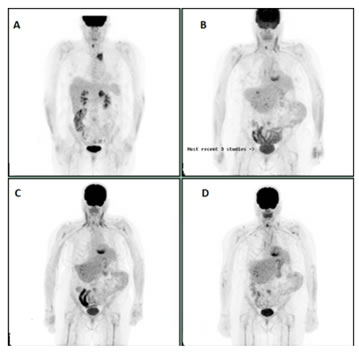

A 54-year old male who was initially diagnosed with stage IV A squamous cell cancer of hypopharynx in November 2013 was started on induction chemotherapy with Docetaxel/Cisplatin and 5-Fluorouracil (DCF) given bulky disease and subsequently received concurrent chemoradiation with weekly Carboplatin (AUC 1.5) and Paclitaxel (50 mg/m2) with complete response. He later underwent right neck dissection for disease recurrence in the neck in April 2016. PET scan in August 2016 showed recurrent disease in the right neck with left upper lobe FDG avid lung nodule. Biopsy confirmed Squamous cell carcinoma. He was started on Pembrolizumab and received a total of 6 cycles. PET scan after six cycles showed disease progression. Palliative care versus weekly PCC were discussed with the patient. Patient opted for weekly PCC. PET scan performed after six cycles of weekly PCC showed great response and patient is currently receiving maintenance Cetuximab (Figure 3A-3D).

Figure 3: A: Initial study. B: PET scan after 4 cycles of Pembrolizumab. C: PET scan after 6 cycles of Pembrolizumab showing progression. D: Virtual Complete response after 6 cycles of PCC post Pembrolizumab progression.